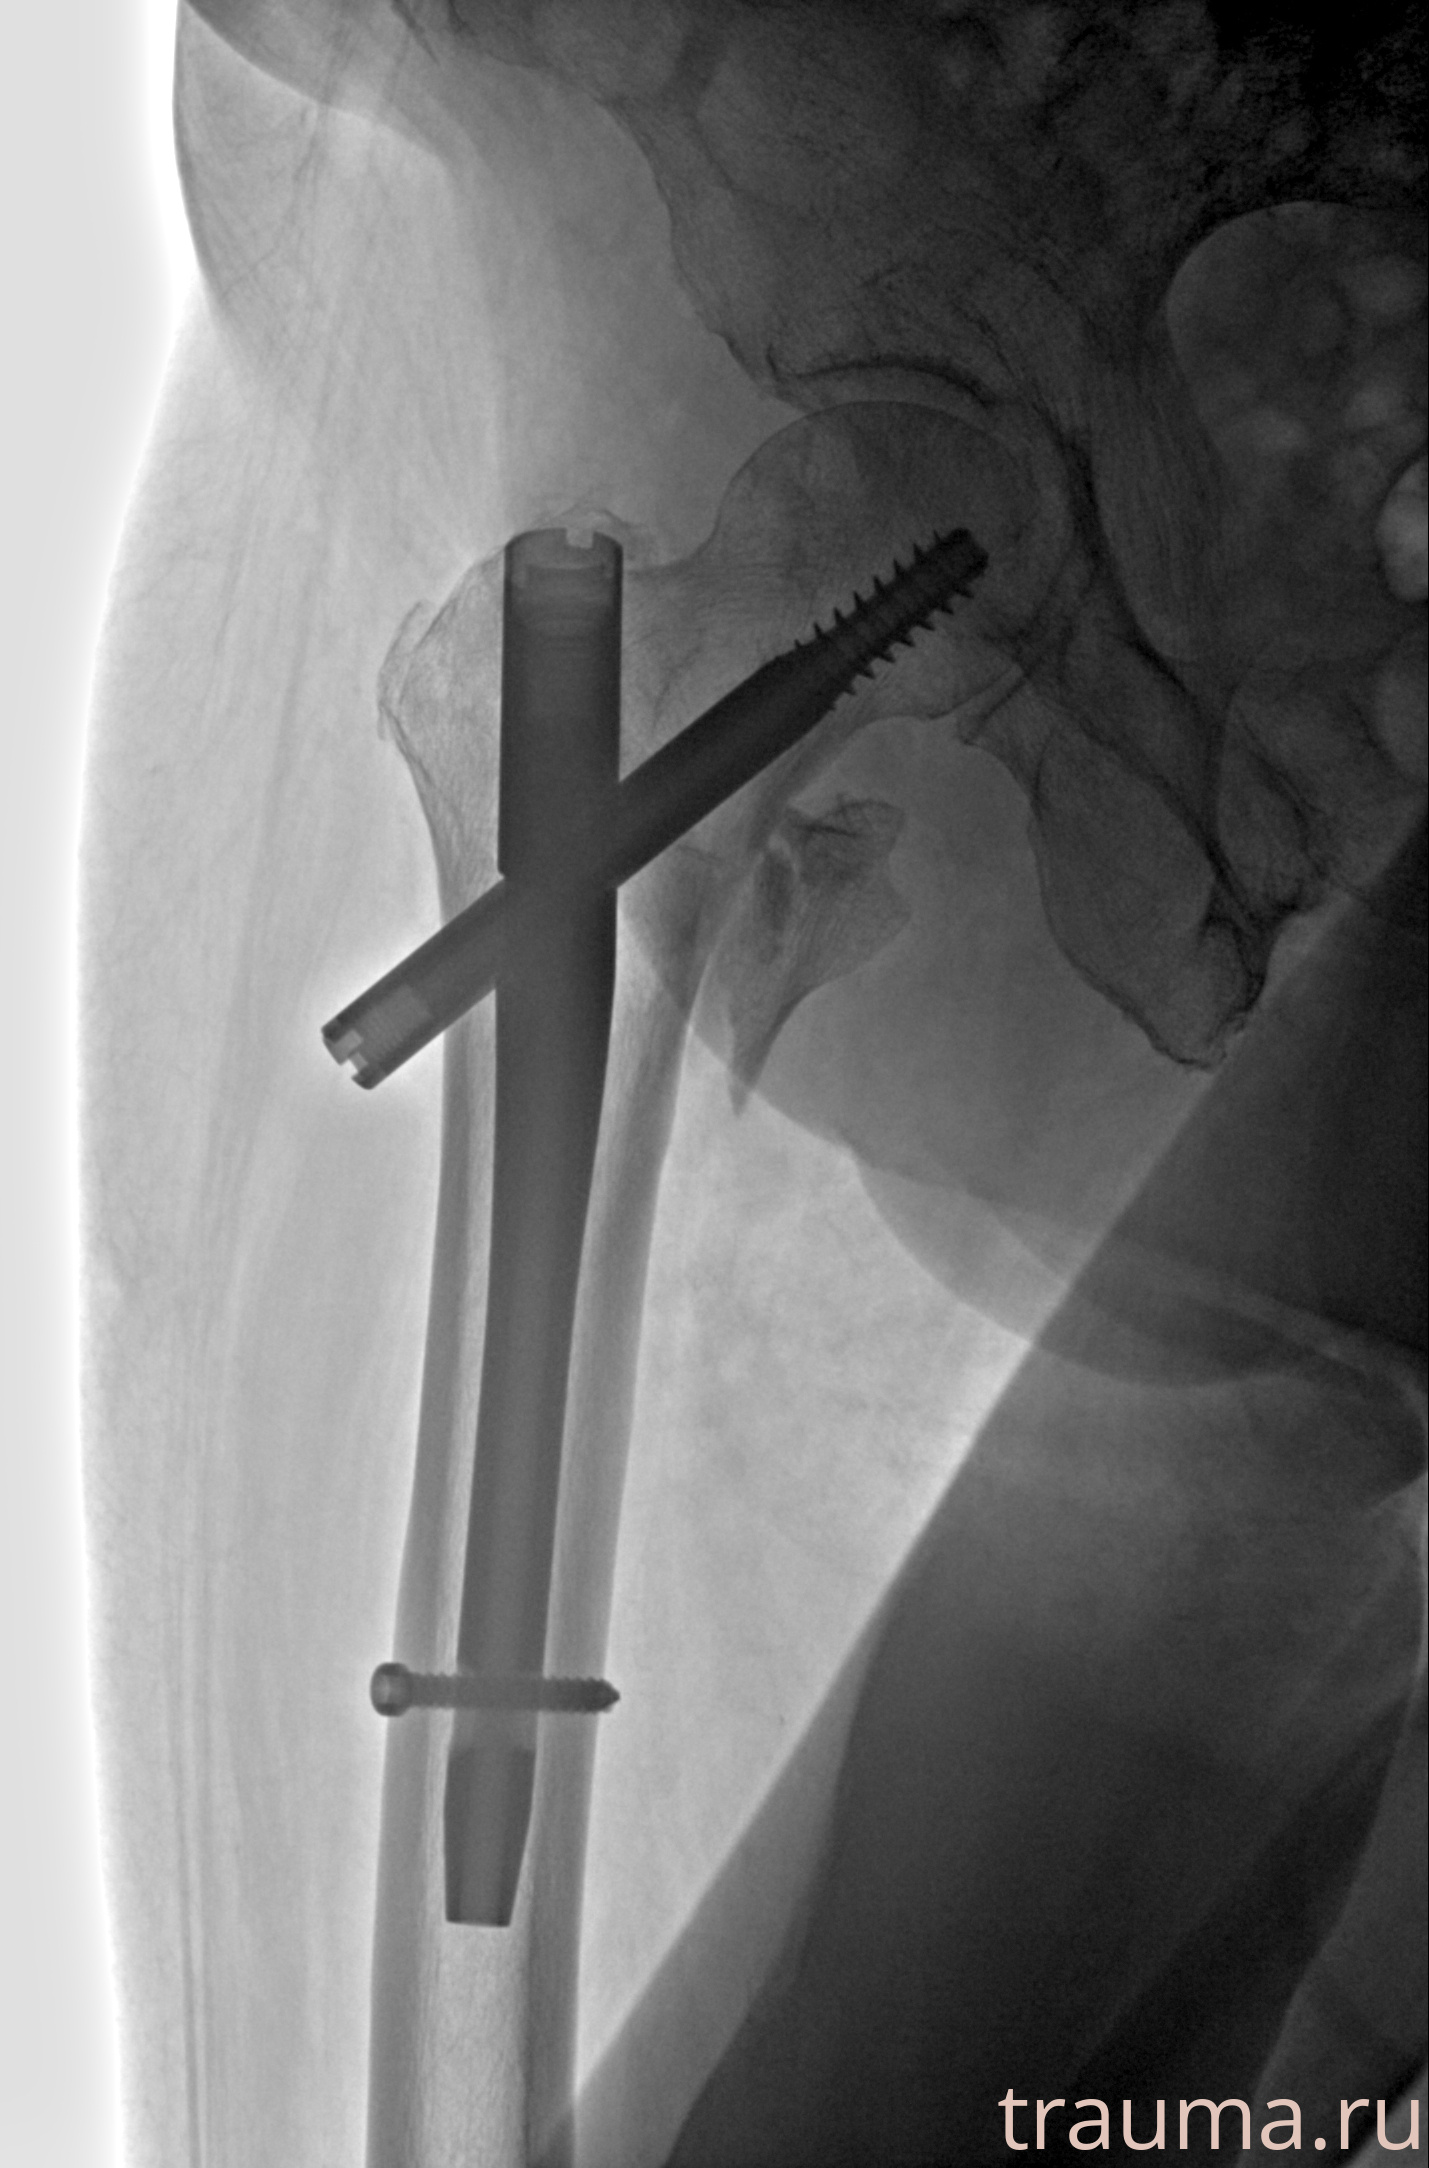

Рентгенограммы

Рентген на дому: по вашему адресу приезжает врач-рентгенолог, травматолог-ортопед с мобильным рентгеновским аппаратом, проводит диагностику травмы или заболевания, делает необходимые рентгенограммы, дает рекомендации по дальнейшему лечению. Получить качественные снимки в домашних условиях возможно благодаря уникальной методике, разработанной МосРентген Центром для института  Склифосовского